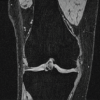

The reported case is for a 77-year-old Indian lady who presented with recurrent progressively enlarging ankle mass of 19 years duration, for which she underwent surgery 15 years ago. Even though the Swelling is not associated with pain, it is progressively increasing in size, limiting her range of motion in the left ankle. On examination, a firm, non-tender mass is present on the medial side of the left ankle joint without any signs of inflammation like redness or the local rise of temperature. The mass was non-compressible, immobile, and did not transilluminate. A scar was present over the swelling, which healed by primary intention (Fig. 1). The clinical diagnosis suggested a soft-tissue ganglion. A radiograph showed soft-tissue opacity over the anteromedial aspect of the tibiotalar joint (Fig. 2). Magnetic resonance imaging (MRI) revealed a well-defined, multilobulated, encapsulated lesion at the tibiotalar joint’s medial side, with intra- and extra-articular components and an analogous signal intensity to fat (Fig. 3).